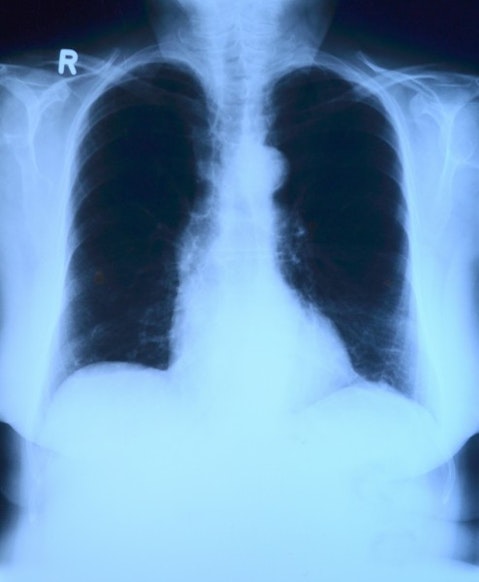

1. X-Rays

It was in 1895 when one of the most important medical accidental scientific discoveries and invention was made by mistake. Wilhelm Röntgen was examining effects of the passing of electrical current through gasses and realized he had found out the electromagnetic radiation which can go through almost any solid matter. His discovery was immediately recognized as a revolutionary thing in medicine, and it had remained like that ever since.